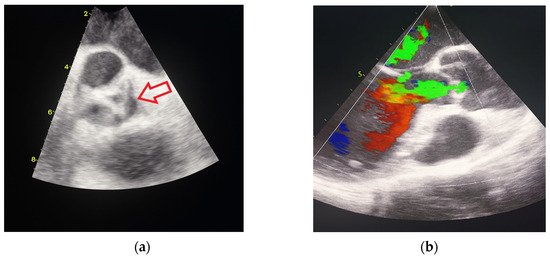

Background and Clinical Significance: This article explores the application of fetal speckle tracking technology in evaluating critical aortic stenosis (AS) in fetuses, highlighting its potential for predicting neonatal outcomes. Case Presentation: We present two cases of fetuses diagnosed with critical AS [...] Read more.

Background and Clinical Significance: This article explores the application of fetal speckle tracking technology in evaluating critical aortic stenosis (AS) in fetuses, highlighting its potential for predicting neonatal outcomes. Case Presentation: We present two cases of fetuses diagnosed with critical AS and associated complications at late gestation. Case 1 demonstrated preserved left ventricular function, as indicated by favorable global strain (GS), fractional area change (FAC), and ejection fraction (EF) values, despite critical conditions. This infant underwent successful postnatal interventions and was discharged after an extended NICU stay. In contrast, Case 2 exhibited severely compromised left ventricular function with significantly reduced GS, FAC, and EF parameters, leading to a tragic outcome despite intensive management. Conclusions: Our findings suggest that innovative echocardiographic parameters such as GS, FAC, and EF for the left ventricle are crucial in prognostic evaluations for fetuses with critical AS. The study underscores the importance of advancements in fetal cardiology and the need for further research to enhance prognostic assessments and improve clinical outcomes in affected neonates. Full article